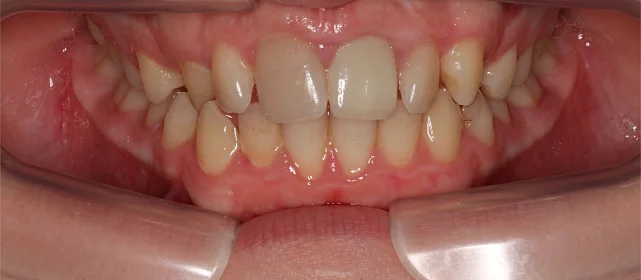

Неровные зубы, неправильный прикус.

Нарушение соотношения челюстей и неправильное положение зубов — ряды смыкались некорректно, зубы стояли со смещением.

Проблема: Пациентка обратилась с жалобами на неровные зубы и неправильный прикус. Челюсти смыкались некорректно, зубы стояли со смещением. Часть зубов нуждалась в восстановлении коронками, но ставить их на кривой ряд с неправильным прикусом значит заведомо сократить им срок службы. Нагрузка будет распределяться неравномерно, и конструкции быстро выйдут из строя. Поэтому первый этап — ортодонтия, второй — протезирование.